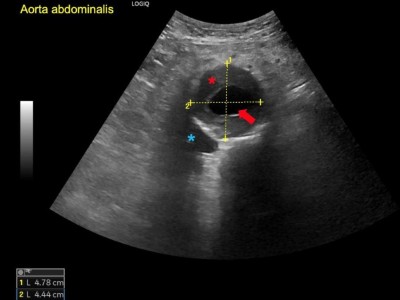

Wie hängen Aneurysma, Sepsis und Kolonkarzinom zusammen?

Ein 92-jähriger Mann stellt sich mit progredienter Dyspnoe, starken retrosternalen atemabhängigen Schmerzen und Fieber vor. Das Thorax-CT zeigt ein Aortenaneurysma mit einer Dissektion und periaortalem Gas. Liegt die Ursache in der Sepsis, die einige Monate zuvor aufgetreten ist – und wie ist die weitere Behandlung verlaufen?

Marginalvene Typ IV/© Gebhardt C et al. / all rights reserved Springer Medizin Verlag GmbH, OCT der Papille am linken Auge/© Jandewerth T et al. doi.org/10.1007/s00129-024-05289-9 unter CC-BY 4.0, Angiogramm bei Bauchaortenaneurysma/© Belezapoy / Stock.adobe.com, PET-CT Aortenaneurysma/© Novoa Usme M.M. et al. / all rights reserved Springer Medizin Verlag GmbH, Zerebrales Aneurysma/© Springer Medizin Verlag GmbH, Übergabe Notfallpatient vom Rettungsdienst an Notaufnahme/© andresr / Getty Images / iStock (Symbolbild mit Fotomodellen), Arzt übergibt Patient Medikamente/© joyfotoliakid / stock.adobe.com (Symbolbild mit Fotomodellen), Frau mit Tablette und Wasserglas in Händen/© fizkes / stock.adobe.com (Symbolbild mit Fotomodell), Operation/© Tobilander / stock.adobe.com (Symbolbild mit Fotomodellen), Blutdruck messen/© (M) sudok1 / stock.adobe.com, Ernährungssonde im Röntgenbild/© Klinischer Image- und Bilddokumentenfokus der Klinik für Radiologie und Nuklearmedizin; Otto-von-Guericke-Universität mit Universitätsklinikum, Magdeburg, Deutschland, Search Icon, Die Leitlinien für Ärztinnen und Ärzte, Darmpolypen/© Hollenbach M et al. / all rights reserved Springer Medizin Verlag GmbH, Arzt erläutert Mammographie-Befund/© Gorodenkoff / stock.adobe.com (Symbolbild mit Fotomodell), Box mit Tabletten/© ekachai050050 / stock.adobe.com (Symbolbild), Blutabnahme/© Grafvision / stock.adobe.com (Symbolbild mit Fotomodellen)